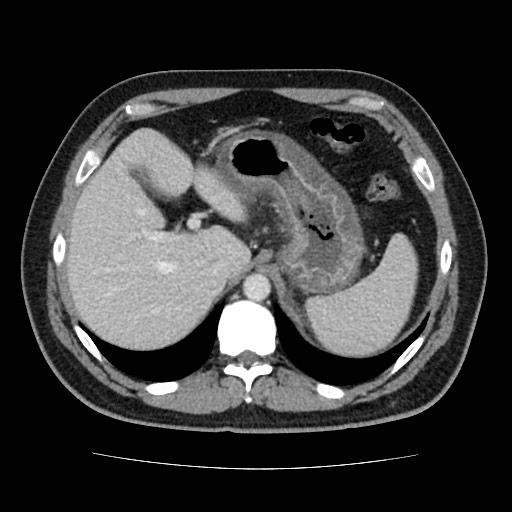

What are the most common Peritoneal Metastases?

- Ovarian cancer

- GIT cancer

- Imaging features

- Greater omentum overlying SB “Omental Cake”

- masses on peritoneal surfaces

- Superior surface of sigmoid colon

- POD

- terminal ileum

- morison pouch

- Gastrocolic ligament

- malignant ascities

- May enhance with Gad as a result of increased permeability of peritoneum